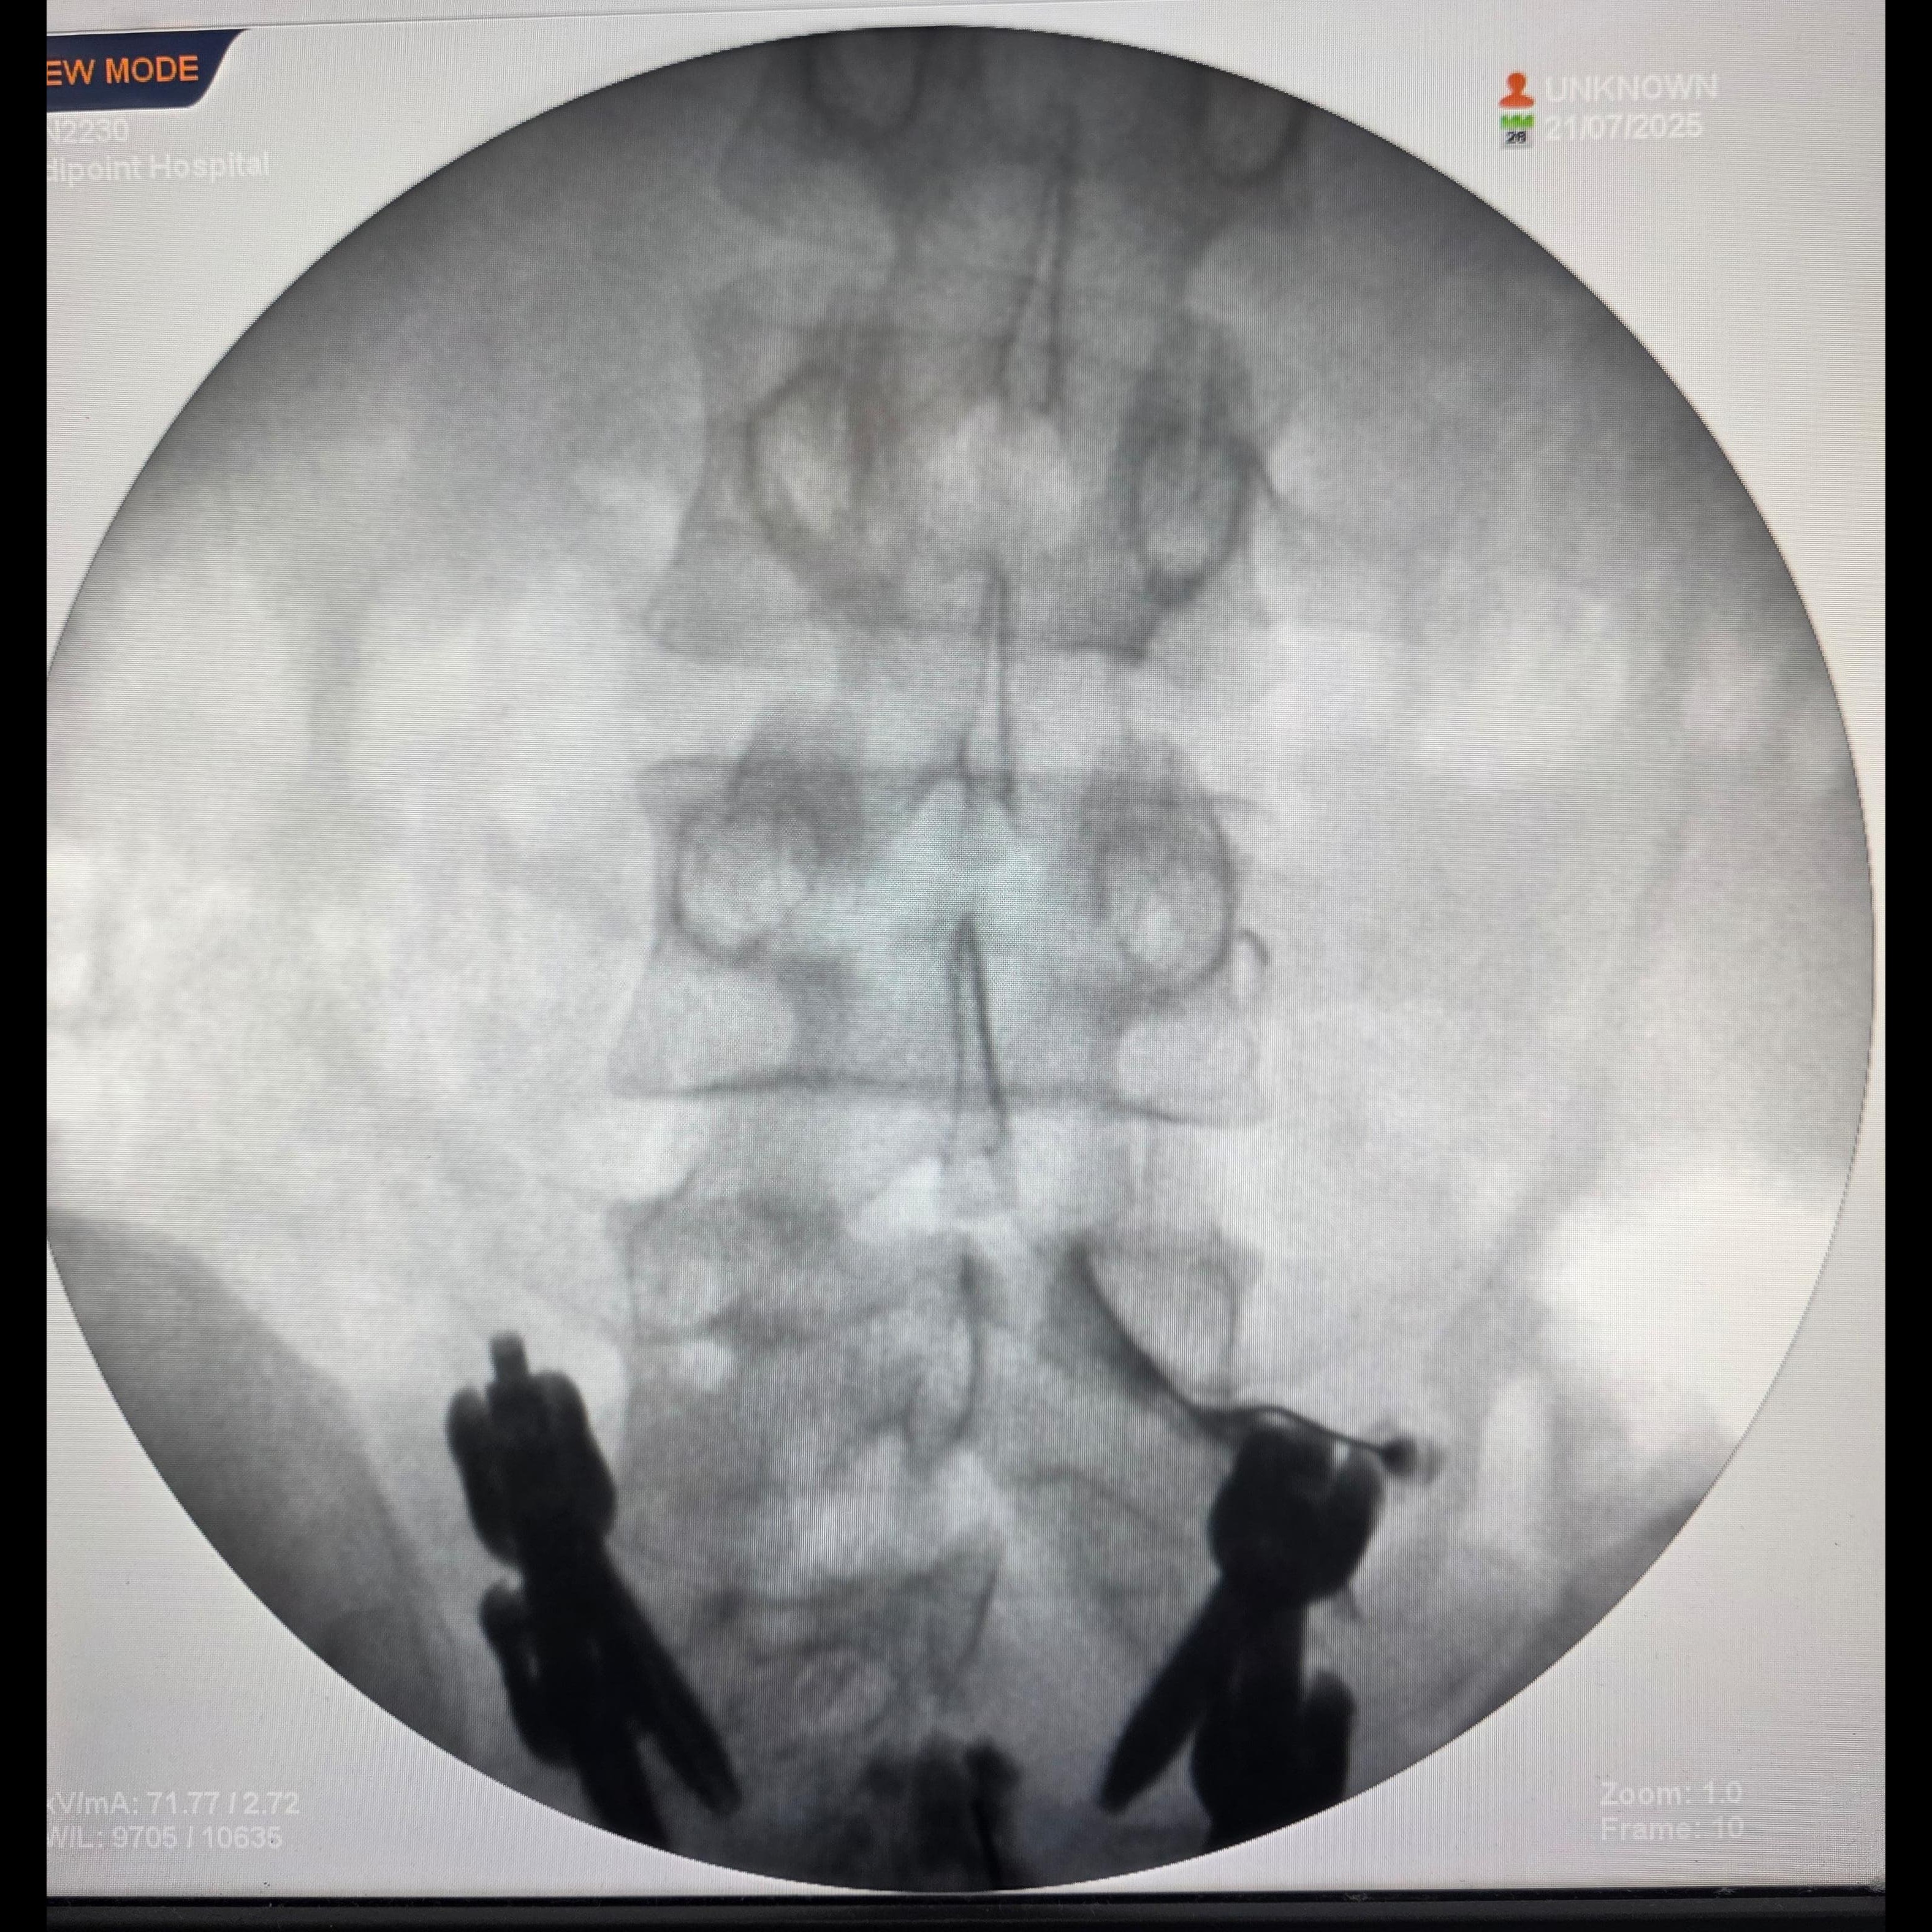

Still in Pain After Spine Surgery? Here's What You Need to Know If you're still suffering from back pain, leg pain, or nerve pain even after spine surgery, you’re not alone. This condition is called Failed Back Surgery Syndrome (FBSS) or post-surgical spine pain, and it affects many patients months—or even years—after surgery. But the good news is: you don't need another surgery. There are advanced, minimally invasive treatments available right here in Pune. Meet Dr. Priya Rathi – Pain & Spine Specialist in Pune Dr. Priya Rathi is one of Pune’s leading pain physicians, helping patients with chronic post-surgical pain using non-surgical techniques like: • Epidural Injections • Caudal Epidural Adhesiolysis • Radiofrequency Ablation (RFA) • Botox Injections for Nerve & Muscle Pain She is known for using image-guided precision techniques that offer long-lasting relief with minimal downtime. Why Does Pain Persist After Spine Surgery? ✅ Nerve irritation or scarring ✅ Epidural fibrosis (scar tissue trapping nerves) ✅ Incomplete decompression ✅ Instability or altered biomechanics ✅ Overactive muscles and myofascial pain Surgery may correct the structure, but pain pathways may remain active—and that’s where Dr. Rathi’s expertise steps in. Advanced Treatments Offered by Dr. Priya Rathi for Post-Spine Surgery Pain 🔹 1. Caudal Epidural Adhesiolysis Purpose: Breaks down scar tissue (epidural fibrosis) that compresses nerves after surgery. How: A special catheter is inserted through the tailbone to deliver targeted medications and release adhesions. Benefit: Immediate pain relief, improved mobility. ✅ Highly effective in Failed Back Surgery Syndrome (FBSS) ✅ Performed under real-time X-ray (fluoroscopy) 🔹 2. Epidural Steroid Injections Purpose: Reduces inflammation around irritated nerves. Used For: Persistent leg pain, back pain, sciatica even after surgery. Benefit: Quick pain relief and improved function. ✅ Minimally invasive. Walk in–walk out procedure. 🔹 3. Radiofrequency Ablation (RFA) Purpose: Deactivates pain-carrying nerves from the spine region. Used For: Facet joint pain, sacroiliac joint pain, or nerve pain post-fusion or decompression. Benefit: Long-term relief (up to 12–24 months) without surgery. ✅ Precision heat treatment under fluoroscopic guidance. ✅ No stitches. No general anesthesia. 🔹 4. Botox Injections for Muscle Pain Purpose: Relieves pain from overactive or tight muscles post-surgery. Used For: Myofascial pain, piriformis syndrome, chronic postural pain. Benefit: Muscle relaxation and reduction in nerve hypersensitivity. ✅ Especially helpful in postural imbalance after spine fusion. Why Choose Dr. Priya Rathi in Pune? ✔ Specialist in Post-Spine Surgery Pain Management ✔ Performs all procedures under ultrasound or fluoroscopy guidance ✔ Non-surgical, daycare techniques ✔ Known for her gentle approach and clinical precision ✔ Trusted by hundreds of patients in Pune and across Maharashtra 🔍 Keywords competitors use: spine pain treatment after surgery, non-surgical pain relief in Pune, RFA in Pune, pain after spine fusion, post-operative back pain treatment Who Should See Dr. Priya Rathi? You should consider seeing a pain specialist if: • You’ve had spine surgery, but pain persists or returns • Pain has shifted from back to legs or vice versa • You’re told 'nothing more can be done' • You want to avoid revision surgery • You want safe, long-lasting relief without hospital stay Book Your Appointment 📍 Sigma Pain & Spine Clinic, Pune 📞9823743726 🌐 www.drpriyarathi.com Don't suffer silently. Relief is possible—even after spine surgery. Let Dr. Priya Rathi, Pune’s trusted pain and spine specialist, help you get back to living pain-free.